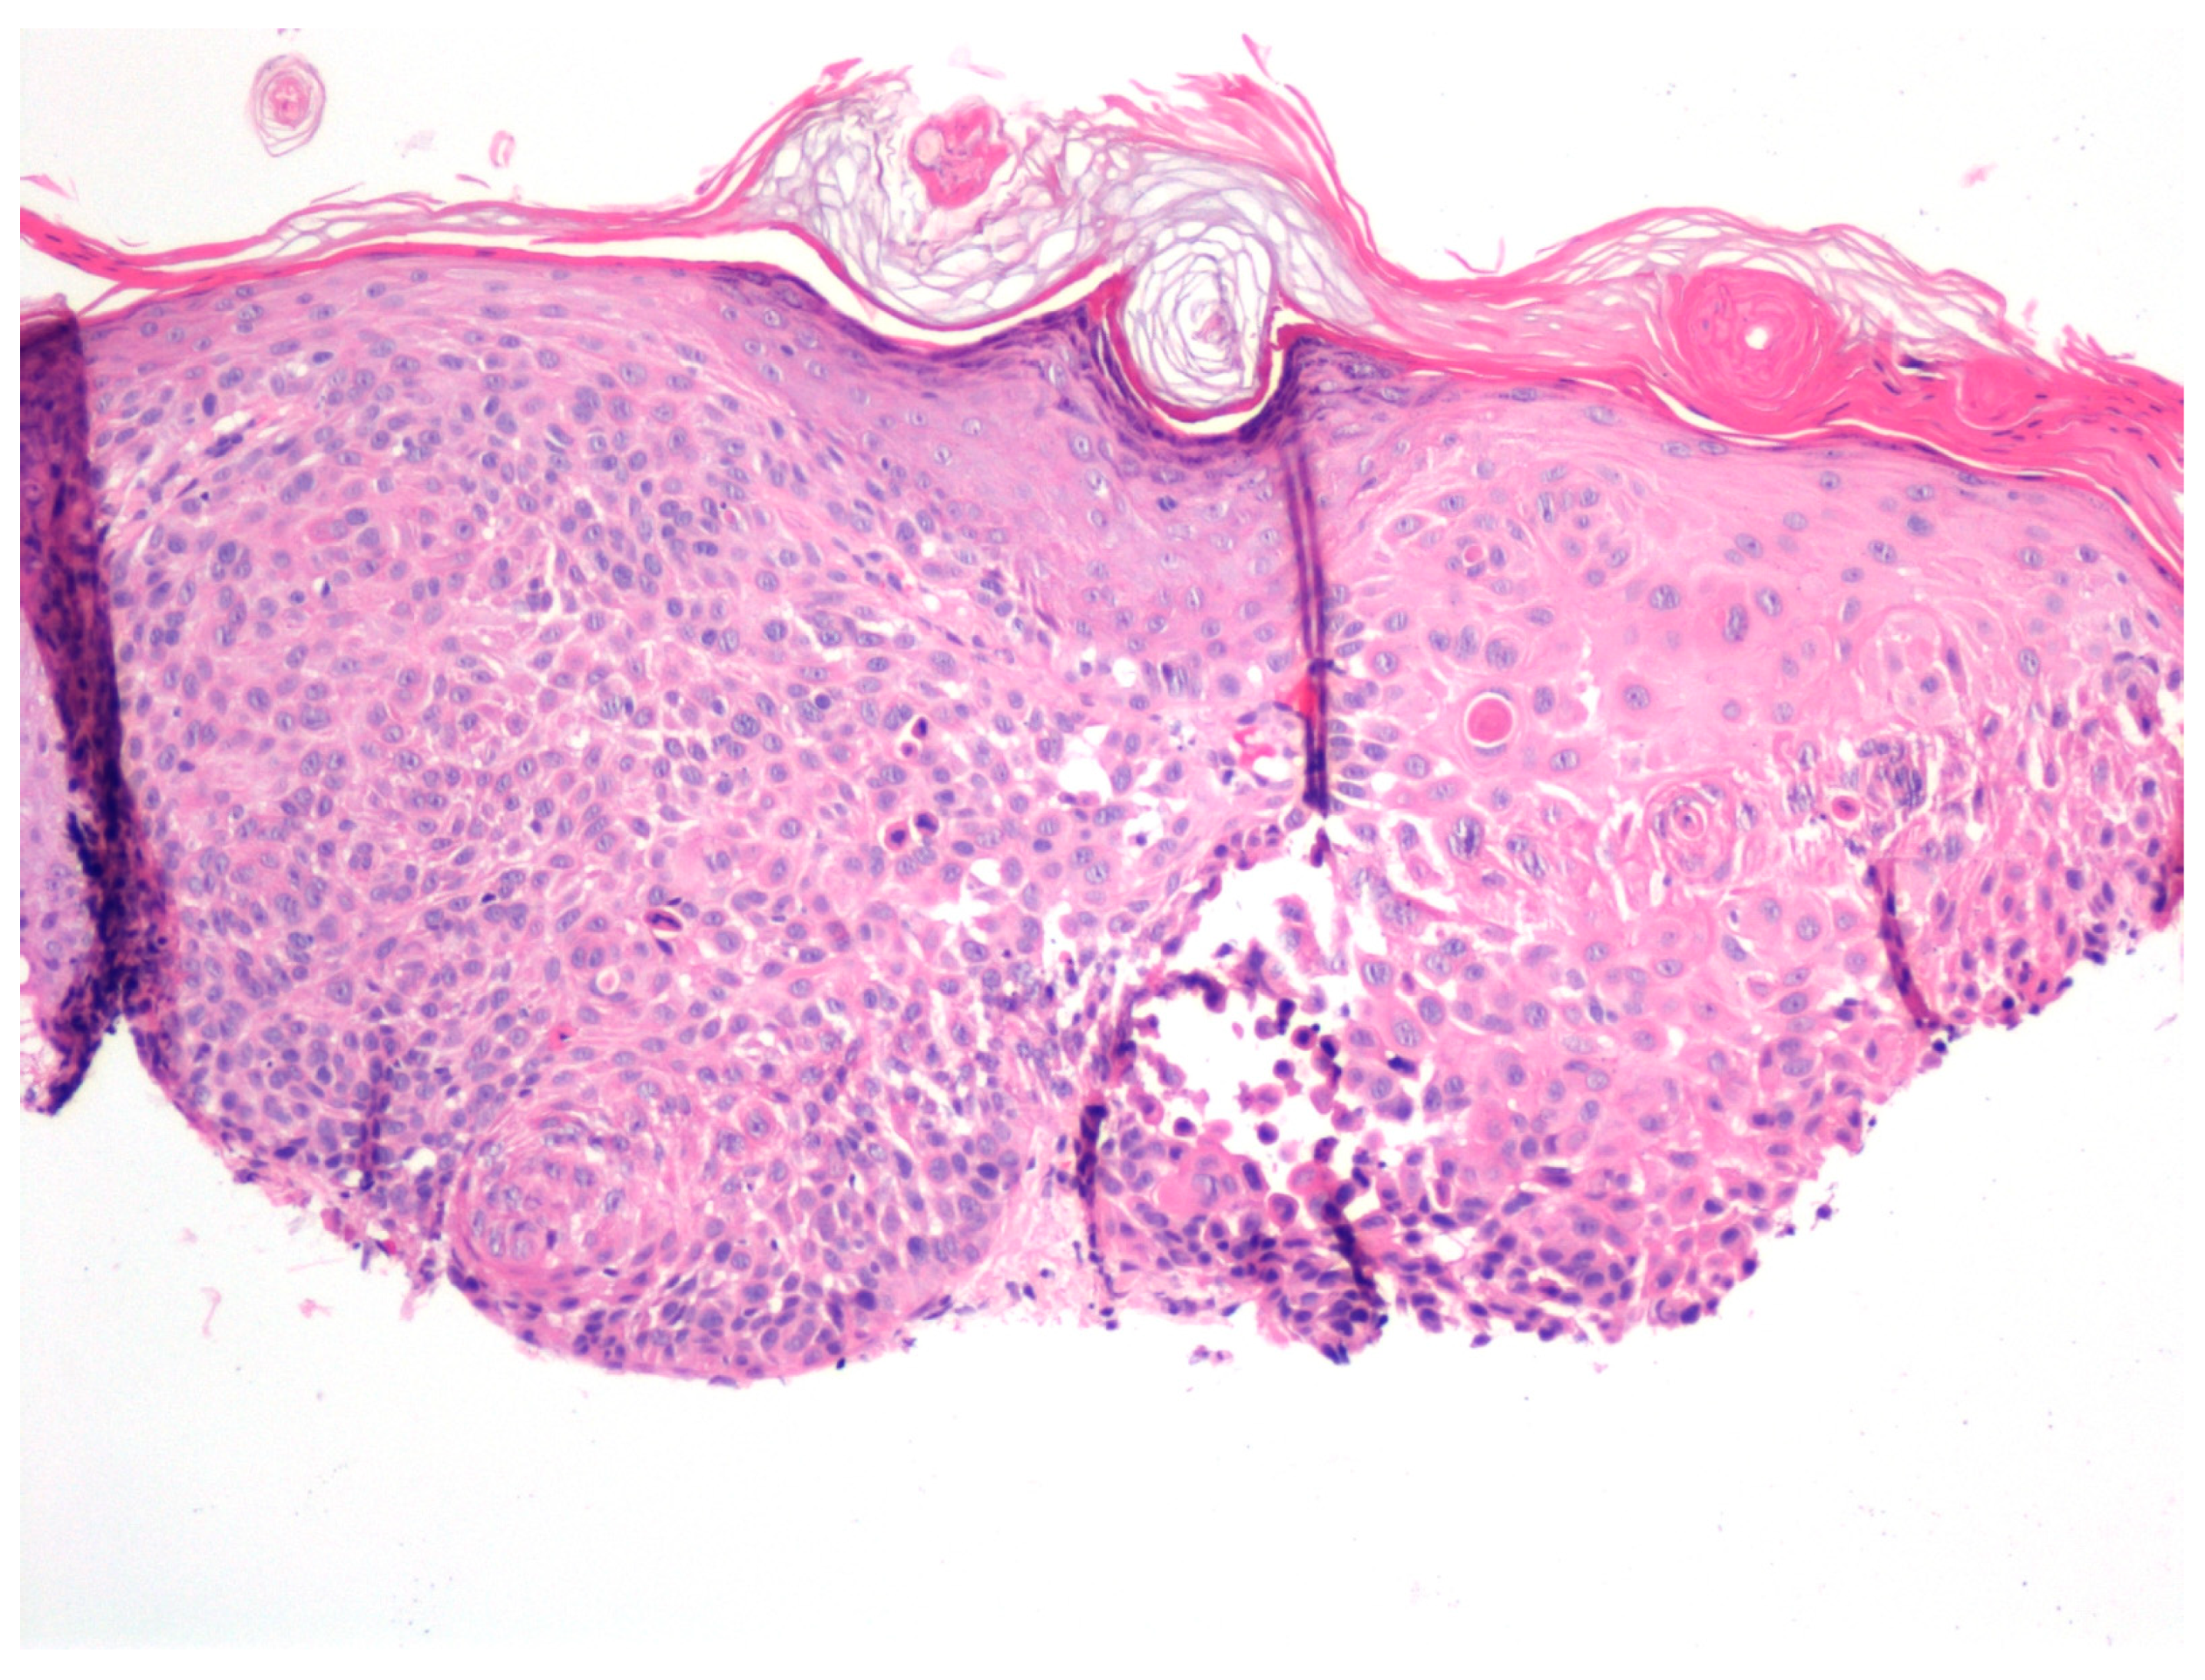

In another patient with a treatment-resistant lesion, the biopsy revealed early invasive cSCC (Figure 5).

Figure 5. Microscopic examination of a biopsy from a therapy-resistant lesion revealed early invasive squamous cell carcinoma of the skin. (H&E: ×100).